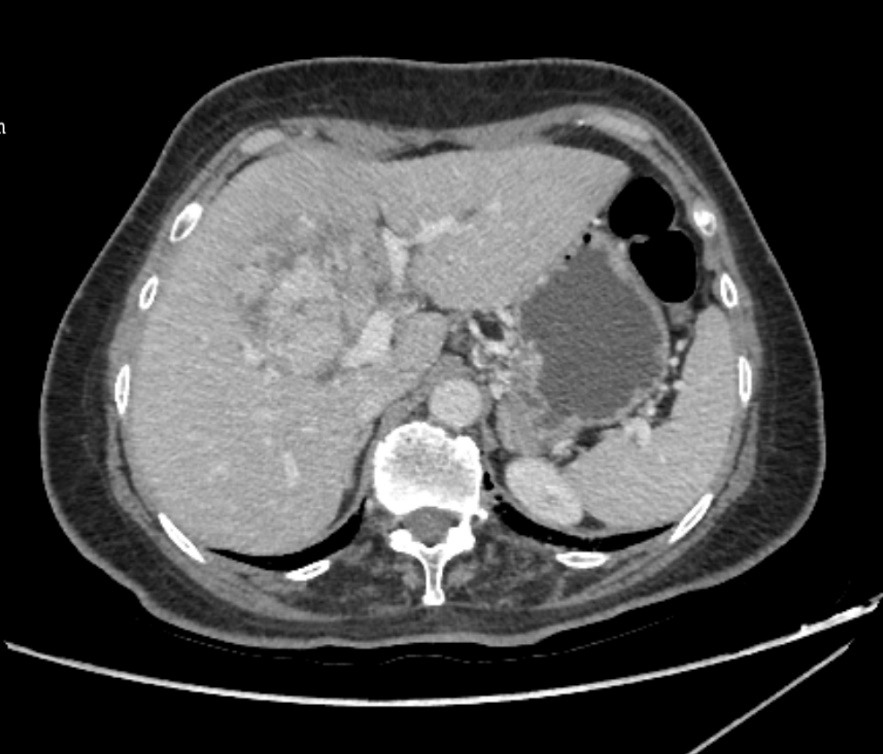

60 岁的李阿姨(化名)在一次体检中意外发现肝脏巨大肿瘤,入院完善相关检查后诊断为原发性肝癌,由于肿瘤负荷较大,且位置特殊,周围比邻重要血管,手术难度极大。科室主任姚红兵组织 MDT 讨论后认为:患者肿瘤较大且比邻重要血管,一期切除无法保证安全手术切缘达到肿瘤根治性切除,决定行 2 个周期新辅助治疗(TACE 联合靶向、免疫治疗)后再行根治性肿瘤切除。

患者经过 2 个周期新辅助治疗后再次术前评估已完全具备手术条件,